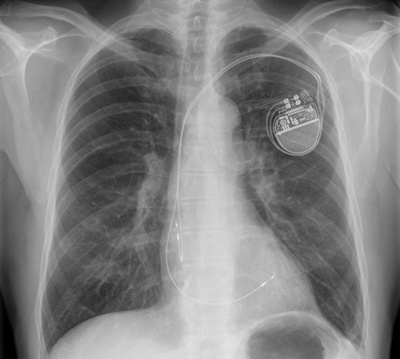

Herzschrittmacher

Auf dem Röntgenbild ist der Herzschrittmacher gut sichtbar. Im Alltag hingegen merkt man kaum etwas davon.

«Nicht einmal zum Briefkasten wollte ich allein gehen.»

Früher war ein Herzschrittmacher noch eine Sensation, heute ist das Einsetzen des kleinen Geräts ein Routineeingriff. Wer einen solchen Taktgeber in der Brust trägt, lebt ganz normal damit.